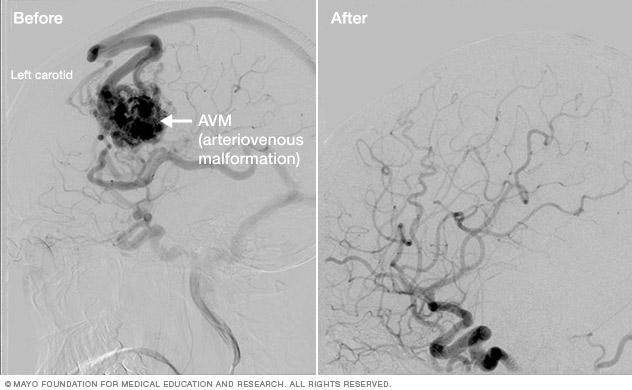

Scans showing brain arteriovenous malformation treatment results.

Brain AVM before and after Gamma Knife treatment

Brain arteriovenous malformation before Gamma Knife treatment (left) and 52 months after the procedure (right)